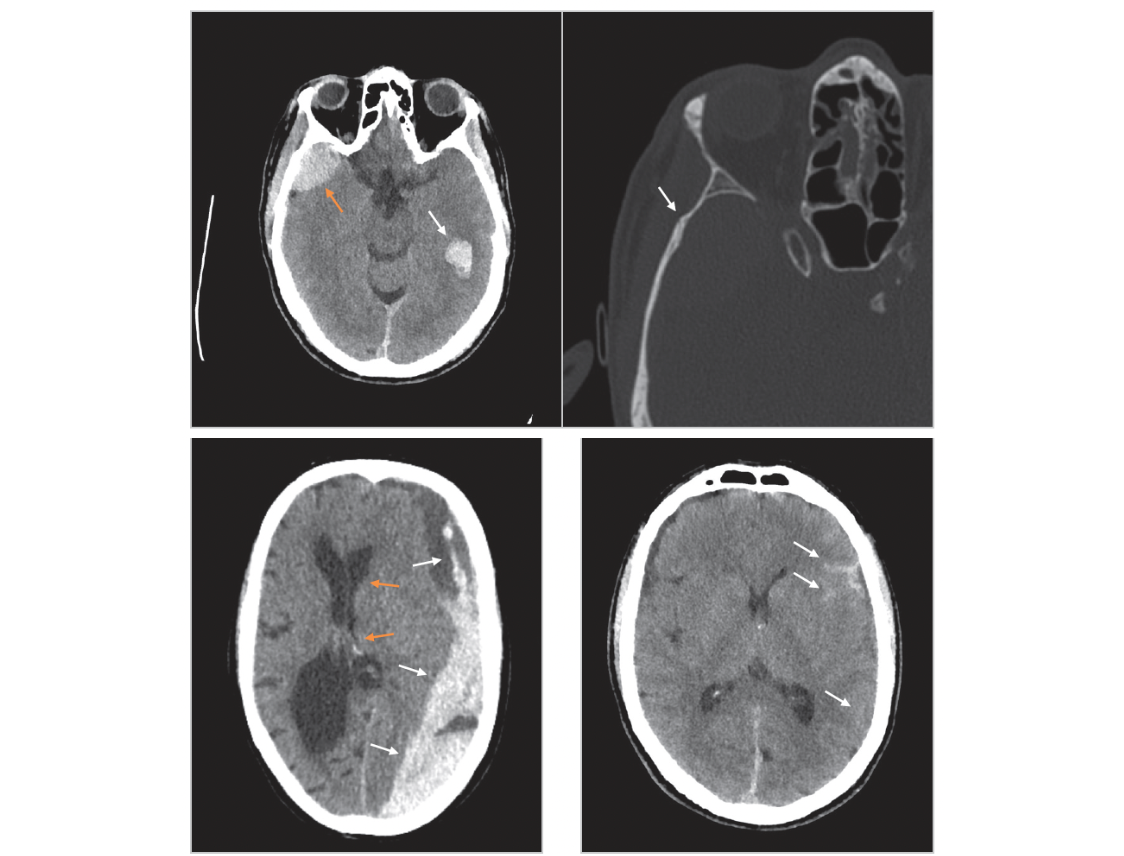

Indicated imaging in intracranial haemorrhage